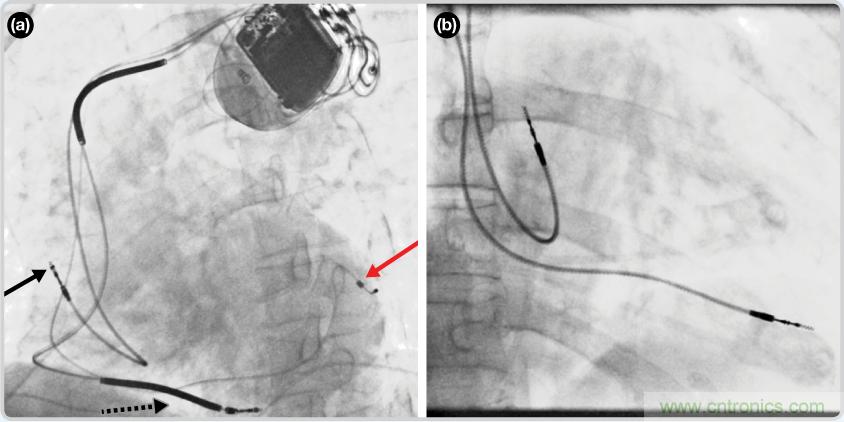

CRT器件在图4(a)中的透视图像中可以看见。医师就是利用这种影像来放置导联线的。对于非专业人士来说,这种影像是很难解读的??梢钥吹叫脑嗟穆掷?mdash;—这是搏动中的心脏的静态视图。起搏器位于右心房上,心脏顶点指向右下方。在这个典型的导联线放置实例中,黑色箭头指向右心房导联线。虚线黑色箭头指向右心室导联线。红色箭头标示的导联线只能看到一部分,这是左心室导联线(红箭头指向电极尖端)。图4(b)展示的是双腔起搏器的典型导联线放置透视图像。右心房导联线指向上方,置于右心房中。右心室导联线则位于右心室顶部。

图4. 起搏器导联线放置的透视图像3 (a). 单腔起搏器;(b).双腔起搏器